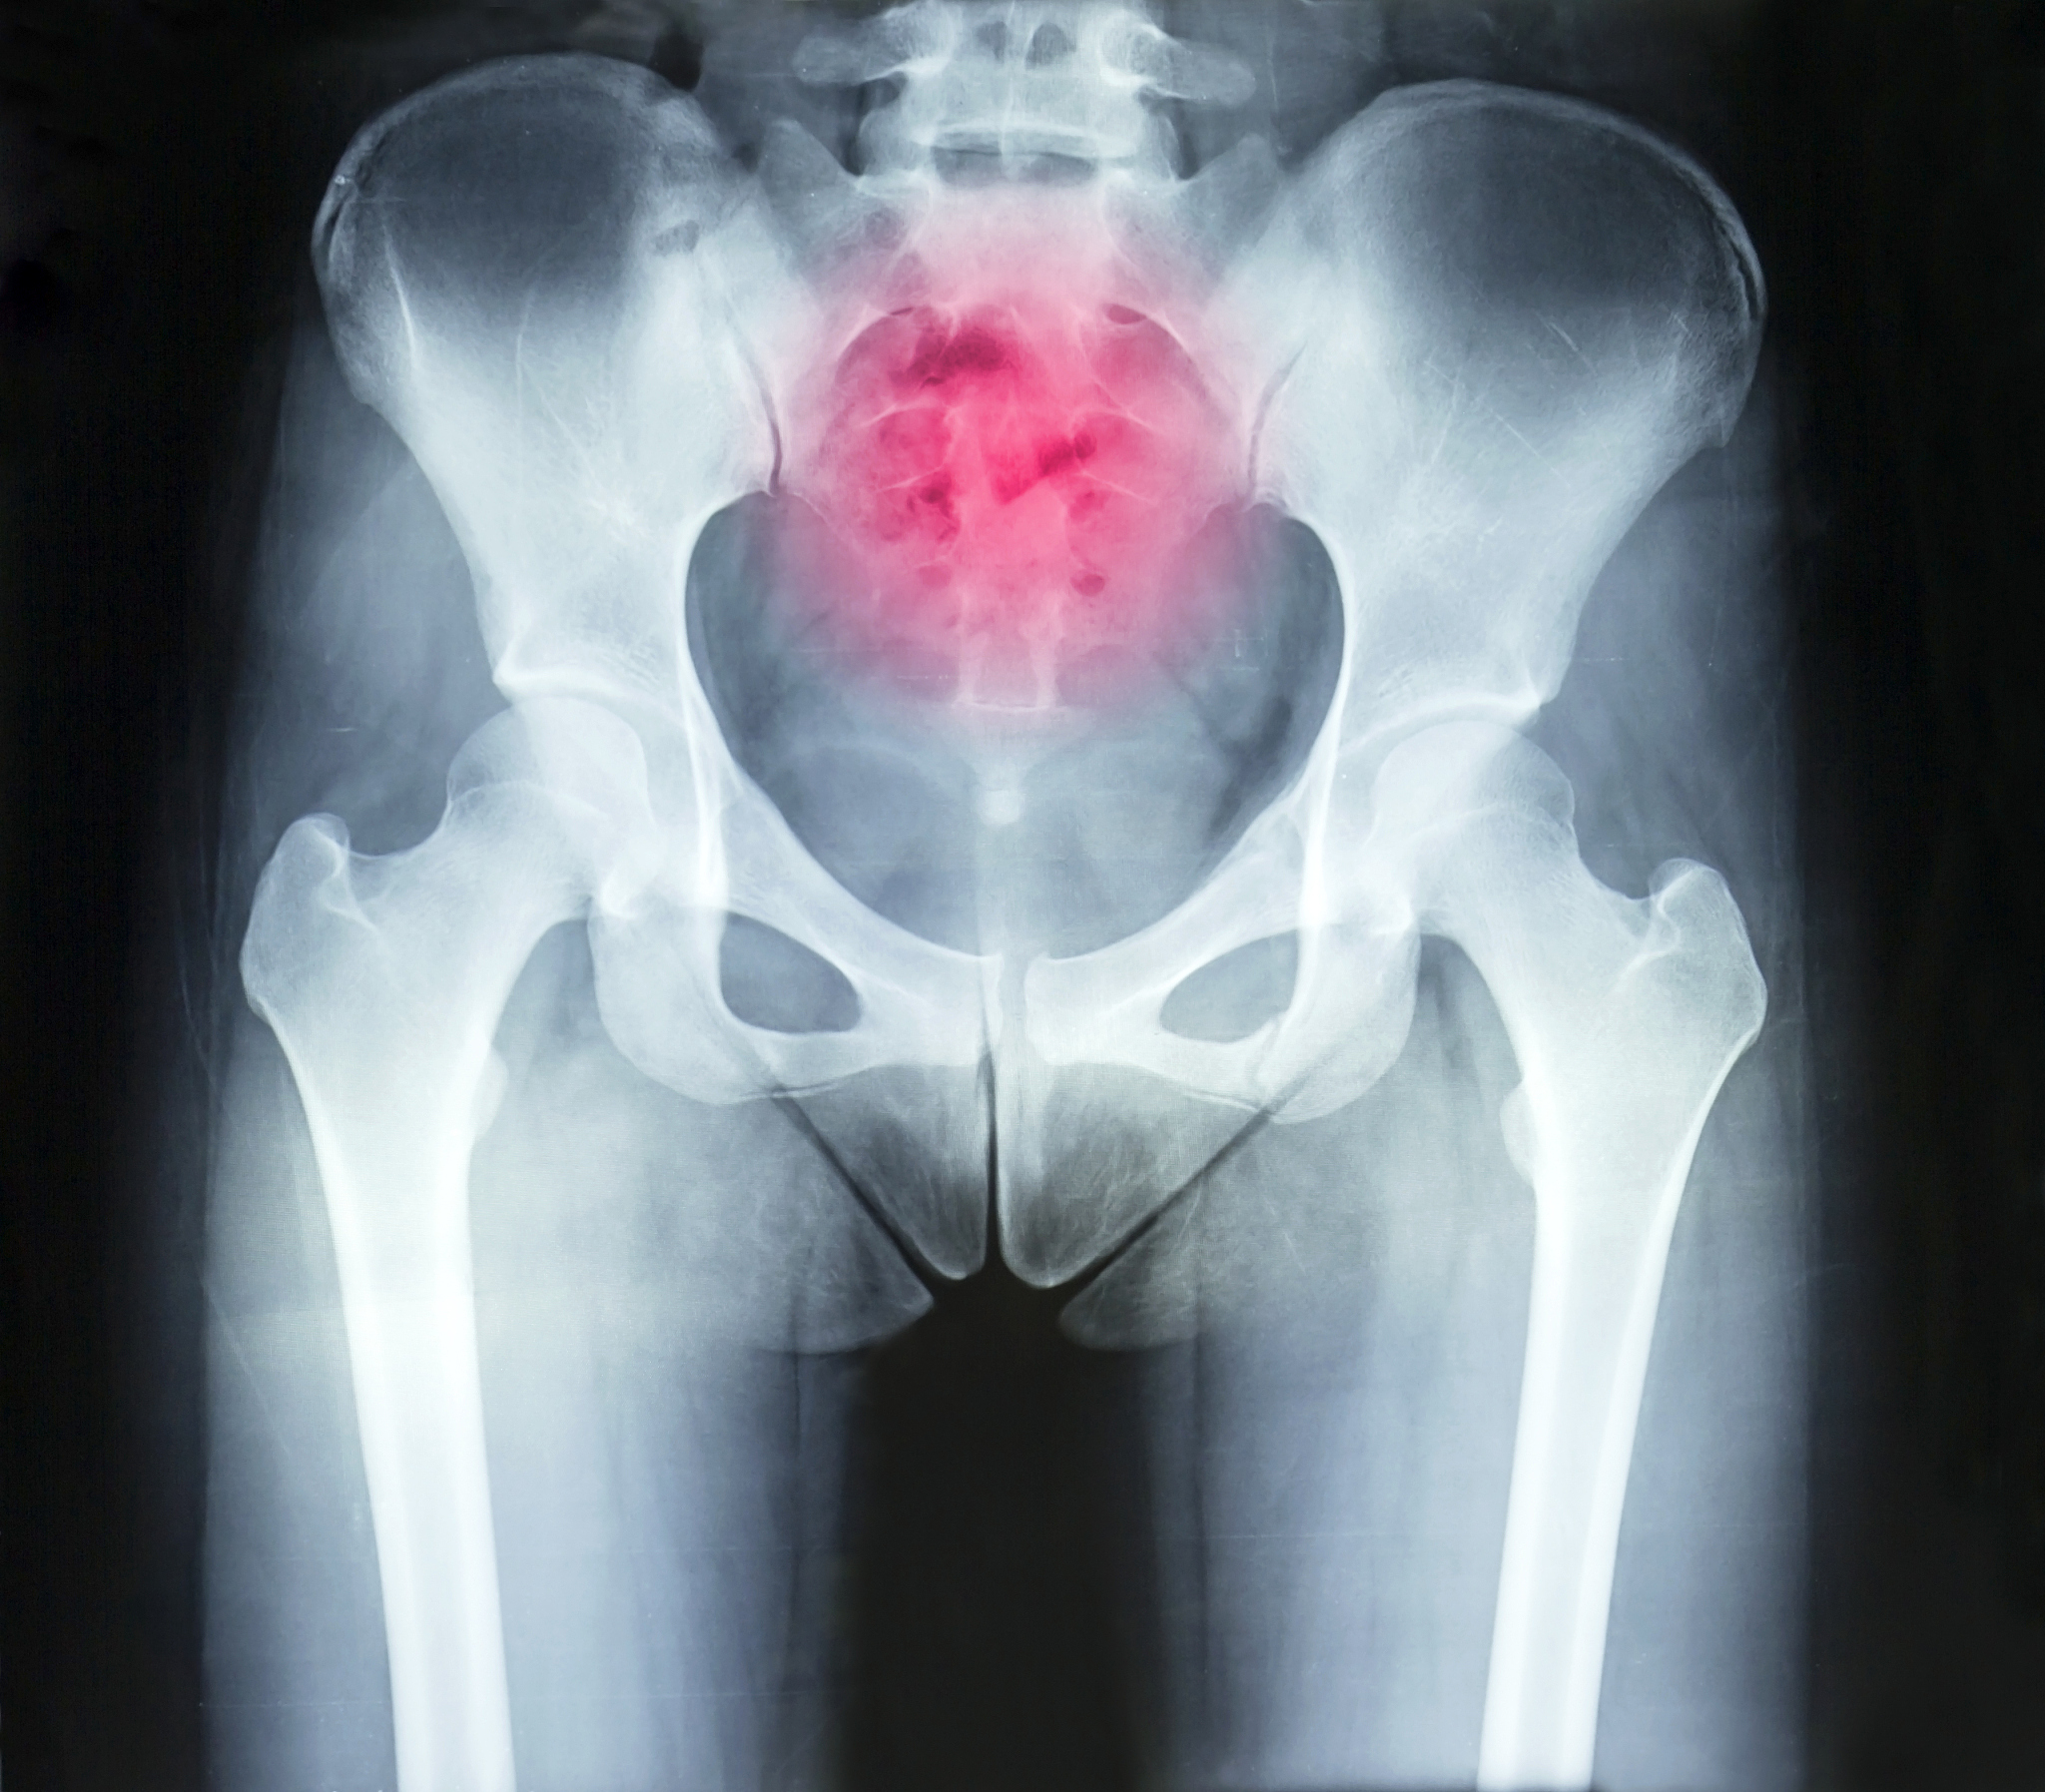

髋部骨折是指髋关节的骨折,通常发生在老年人或骨质疏松的人身上。髋部骨折可以是股骨头的骨折(股骨颈骨折)或股骨颈下段的骨折。

髋部骨折通常由于跌倒、摔伤或意外事故引起。症状包括剧烈的髋部疼痛、无法站立或行走、髋部肿胀和淤血等。

髋部骨折需要紧急治疗,通常需要进行手术修复。手术可以采用内固定(使用金属板、螺钉等将骨折部位固定)或全髋关节置换术(将受损的关节组织替换为人工关节)来恢复髋部功能。

髋部骨折:症状、治疗及康复